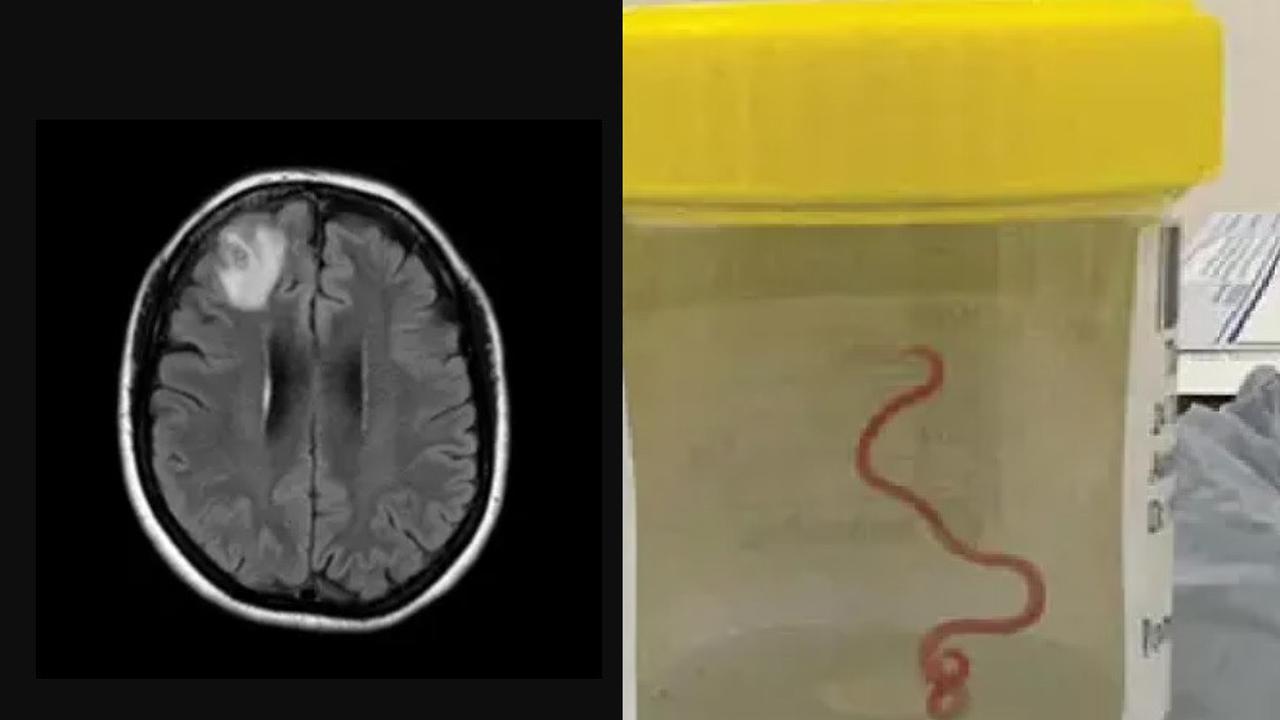

Sejak tahun 2021, wanita tersebut telah mengalami berbagai masalah kesehatan termasuk pneumonia, sakit perut, diare, batuk kering, demam, dan keringat malam. Pada tahun 2022, gejalanya berkembang menjadi depresi dan kelupaan, yang mengakibatkan dokter memerintahkan pemindaian MRI otak. Hasil pemindaian ini mengungkapkan keberadaan kelainan yang memerlukan tindakan pembedahan.

Namun, yang membuat peristiwa ini semakin tidak biasa adalah saat operasi dilakukan, tim bedah menemukan cacing gelang parasit berukuran 8 cm berwarna merah cerah yang hidup di otak wanita tersebut. Cacing ini dikenal sebagai Ophidascaris robertsi yang sebelumnya hanya ditemukan pada ular piton karpet. Ini merupakan kasus pertama kali cacing ini ditemukan hidup di dalam tubuh manusia.

Para dokter dan ilmuwan menghadapi tantangan besar dalam memahami bagaimana parasit ini bisa masuk ke tubuh wanita tersebut. Meskipun dia tidak memiliki kontak langsung dengan ular, dia tinggal di dekat danau yang banyak dihuni oleh ular piton. Kemungkinan besar, telur cacing ini masuk ke tubuhnya melalui tumbuhan yang dikonsumsinya, seperti bayam Selandia Baru yang dia kumpulkan untuk dimasak.